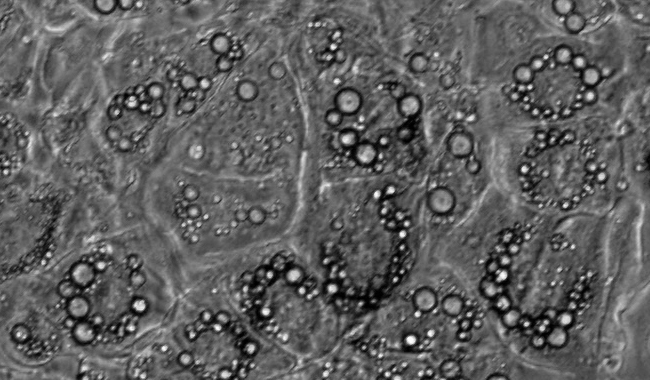

•  脂滴是調節中性脂質儲存的基礎,可以根據脂滴研究代謝的需求。但它們不僅是能量庫,因為這種動態的細胞器是許多生物過程的一部分,如細胞能量平衡和脂質代謝。脂滴法在代謝性疾病的研究,如肥胖、糖尿病和動脈粥樣硬化有重要的作用。

wimLipid圖像分析解決方案是專為增殖,脂滴生長和分布提供了可靠的分析數據,如這些細胞器的數量、覆蓋區域或地區的間隔分布。

分析結果包括:

脂滴個數

脂滴覆蓋面積

平均覆蓋面積

區間分布

單個細胞的脂滴個數和覆蓋面積